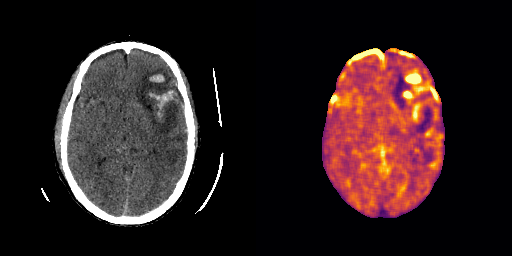

Appendix D Qualitative Results AE

fig:qualitative_ich_ae

ICH

healthy